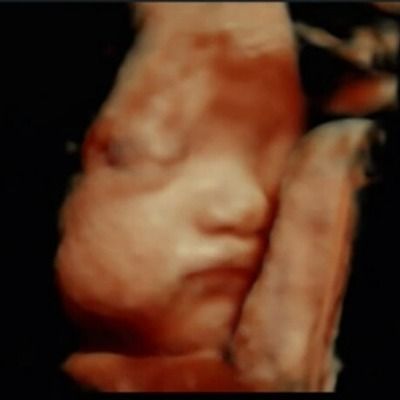

저희 와이프가 지금 임신30주 상태인데요

2달만 있으면 태어날 우리 복덩이♥